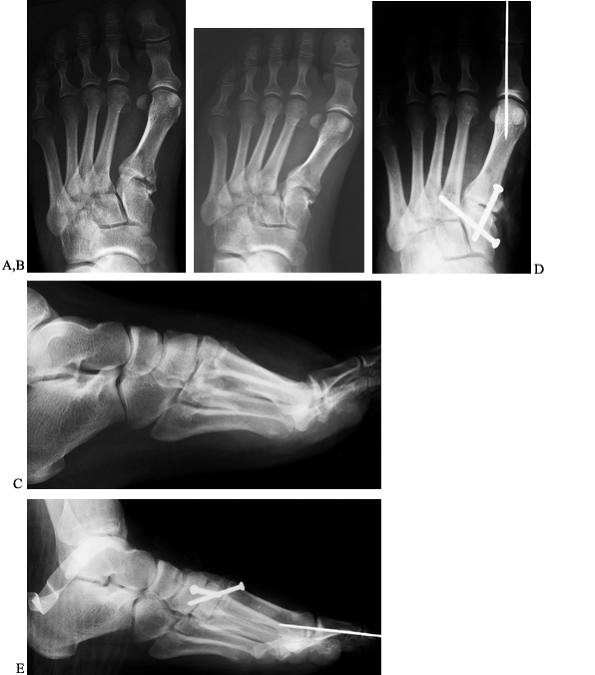

Figure 111.6. Lisfranc’s dislocations with predominantly ligamentous injuries. A: AP views. B: lateral view. C:

Postoperatively on this AP view, two absorbable screws stabilize the

medial column and two K-wires stabilize the lateral column. Arrows show

the path of the screws from the medial cuneiform to the second and

third metatarsals, which cannot be seen because they are radiolucent. D: Oblique view. E: lateral view.

Figure 111.7. AP (A), oblique (B), and lateral (C)

radiographs of bony Lisfranc’s injury, fracture of second and third

metatarsal necks, and displaced sesamoids due to a partly reduced first

MTP dislocation. AP (D) and lateral (E)

postoperative radiographs showing stainless steel screws to stabilize

Lisfranc injury. The first MTP joint was reduced and stabilized with a

K-wire. The second and third metatarsal neck fractures are well aligned.